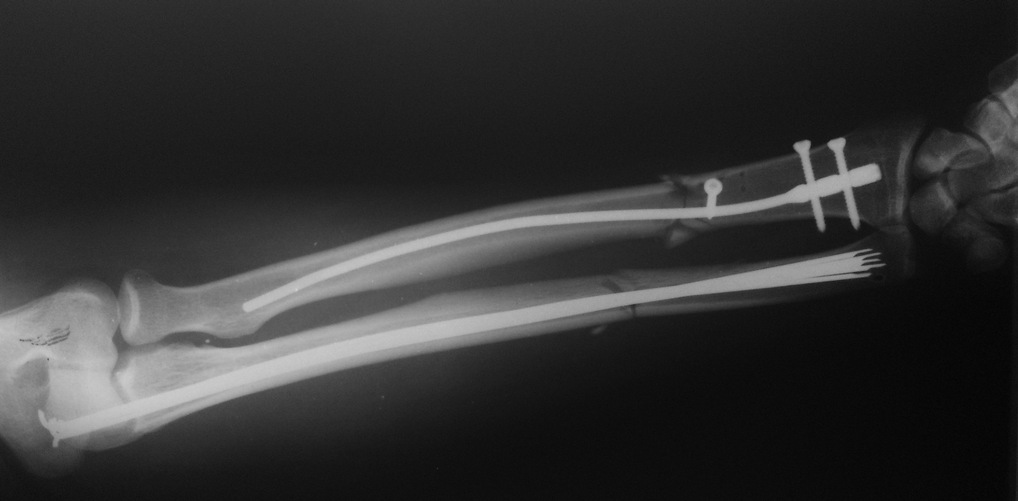

Вложение не в текстовом формате было извлечено&hellip;

Имя     : рис. 4.jpg

Тип     : image/jpeg

Размер  : 61311 байтов

Описание: отсутствует

Url     : http://weborto.net:8080/pipermail/ortho/attachments/20130302/71775e34/attachment-0008.jpg